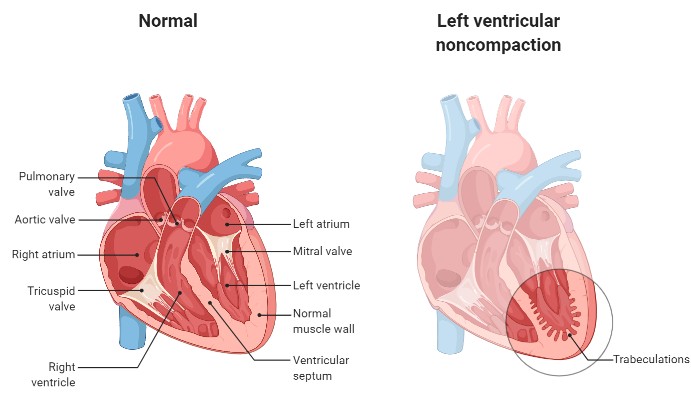

오늘은 정말 많은 분들이 놓치기 쉬운 **치명적인 심장 질환, ‘심근경색’**에 대해 이야기해보려 합니다.심근경색은 말 그대로 심장 근육이 괴사하는 질환으로, 골든타임을 놓치면 생명을 잃을 수 있는 응급상황입니다.

1. 쥐어짜는 듯한 가슴 통증 (흉통)

심근경색의 가장 전형적인 증상입니다.

가슴 중앙 또는 왼쪽 가슴 부근에서 극심한 압박감, 조이는 느낌, 짓누르는 듯한 통증이 나타나며

5분 이상 지속되는 경우가 많습니다. 통증은 휴식으로 사라지지 않고 점점 심해지기도 합니다.